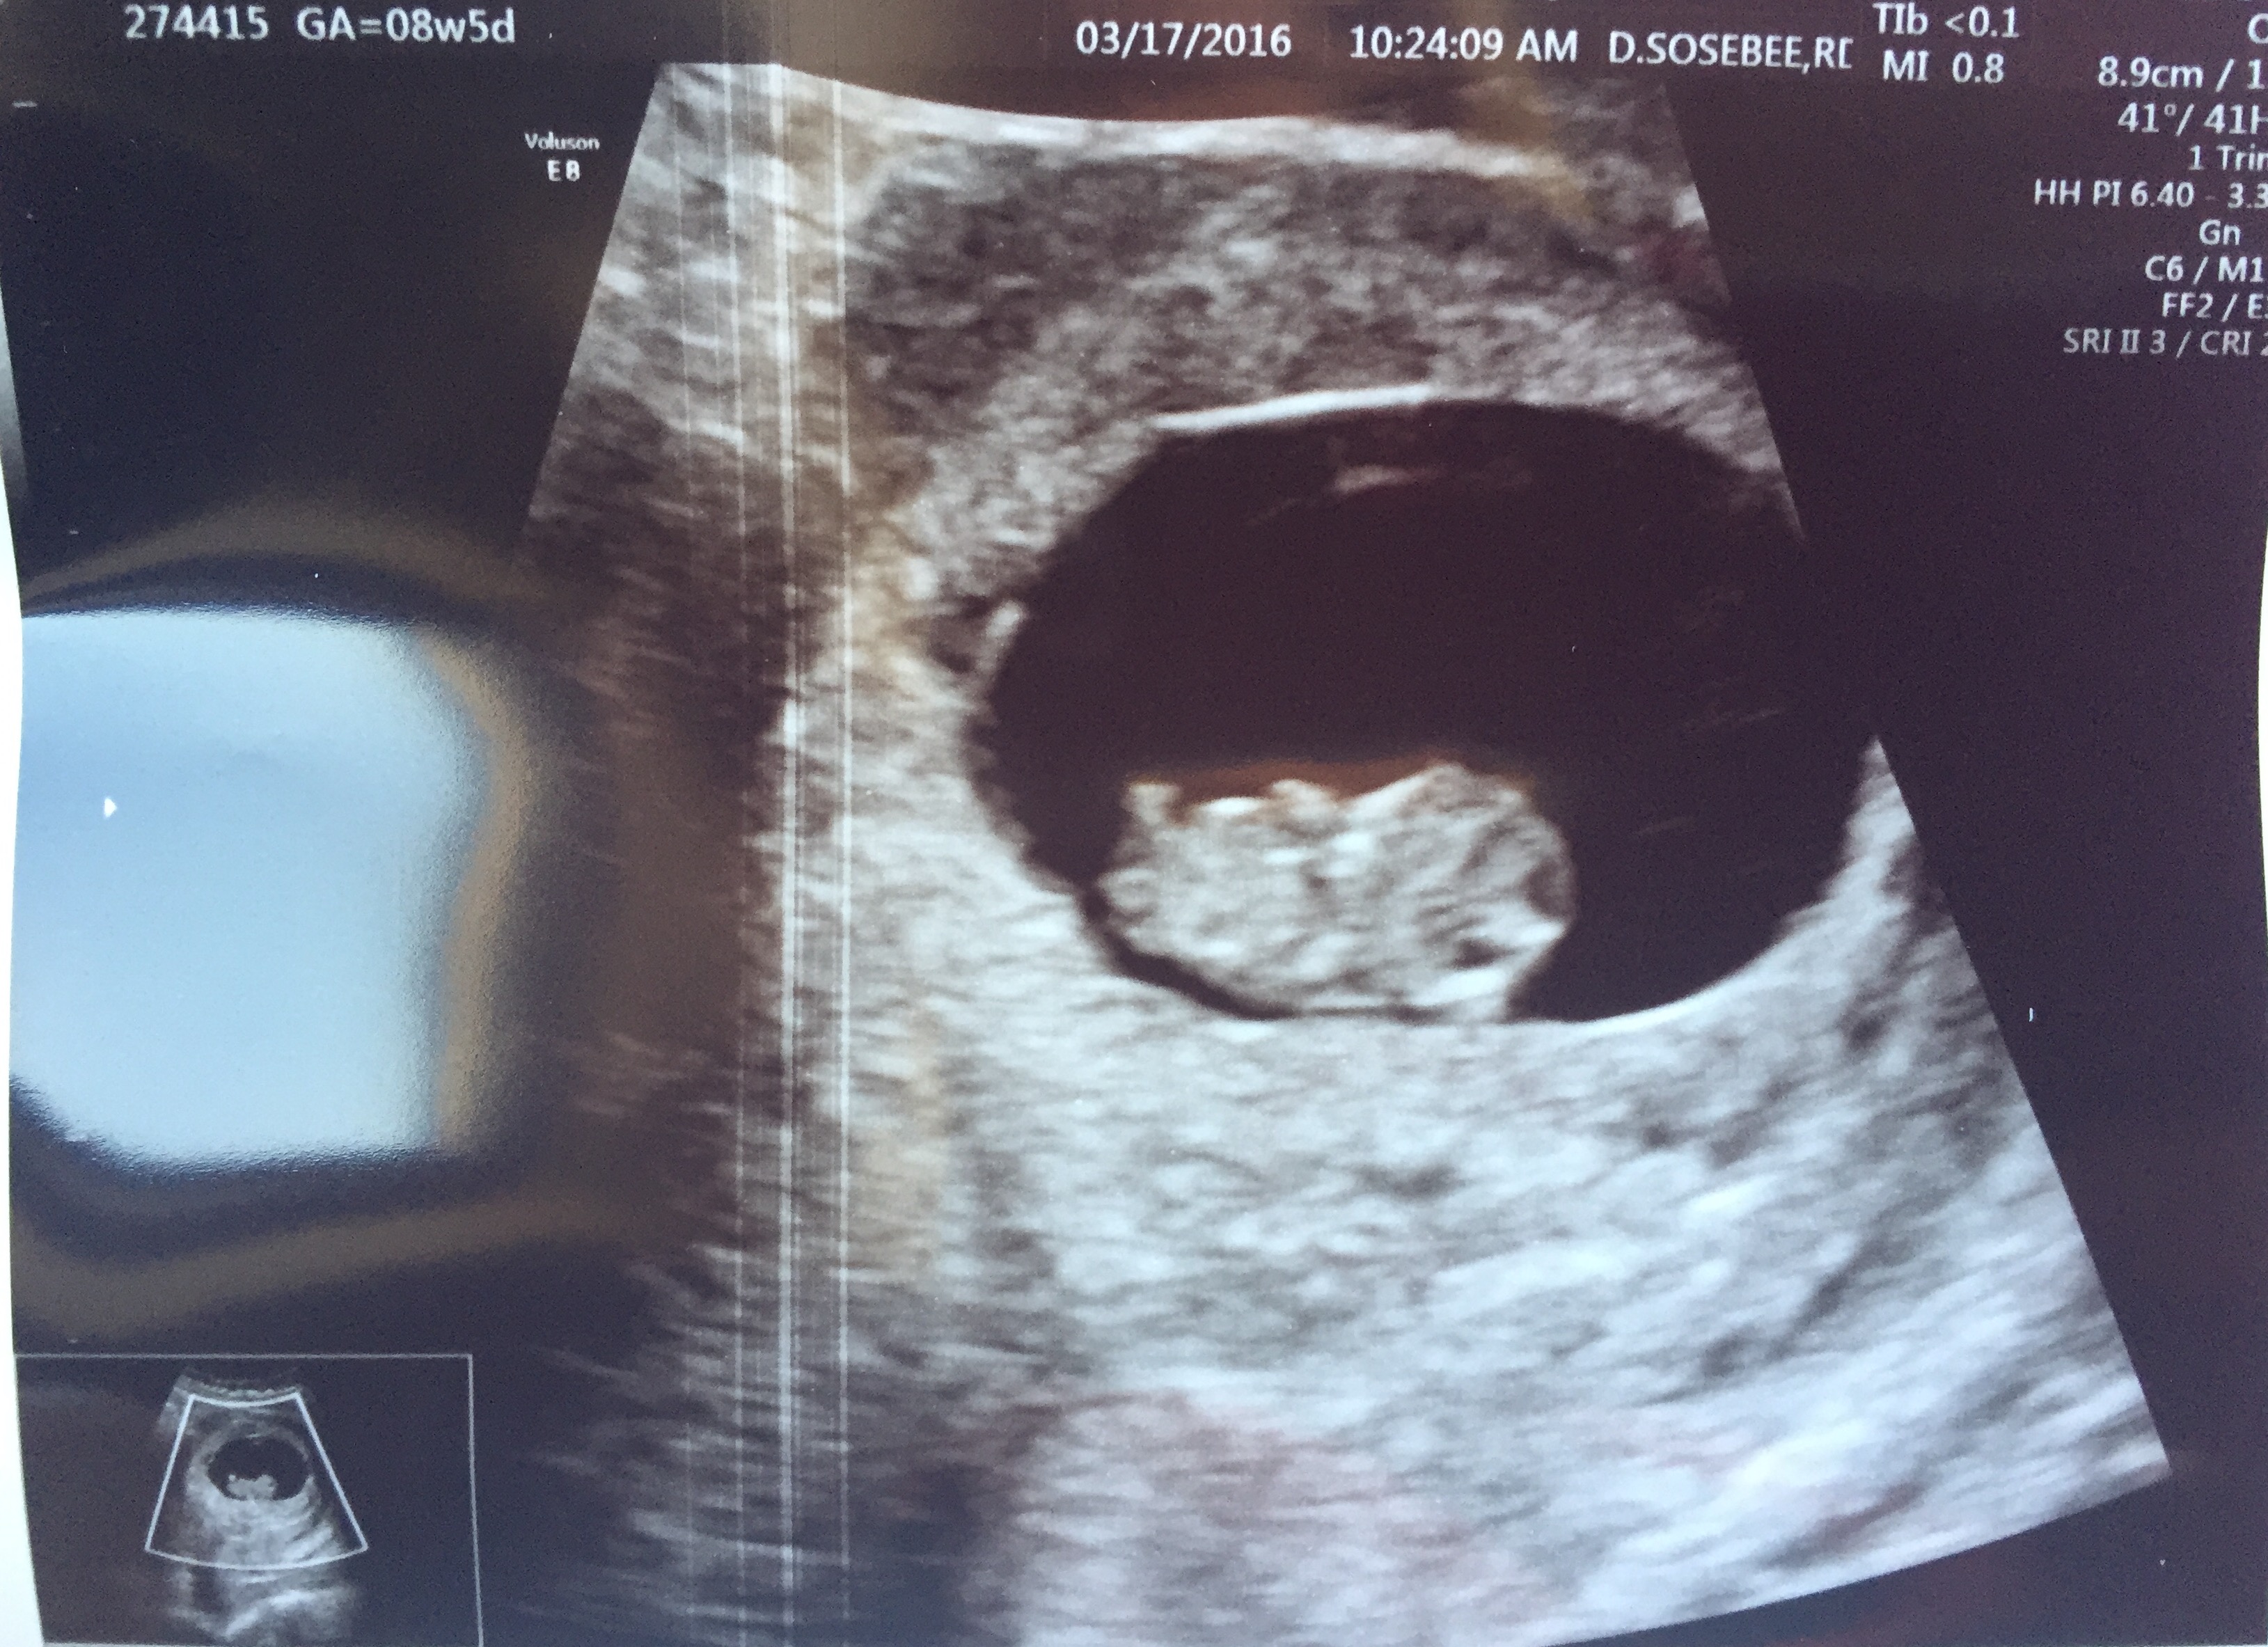

I was 8 weeks 5 days.

Attachment 30893